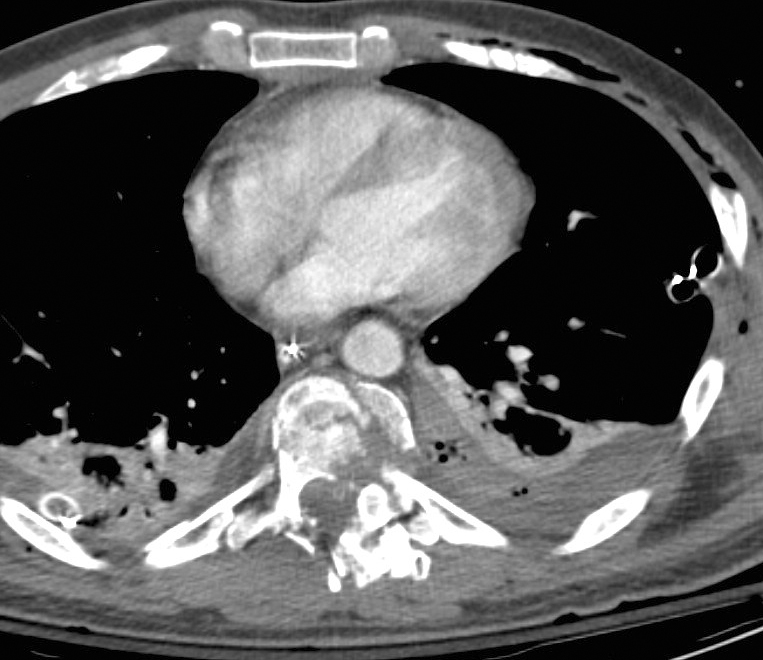

Gallery Blunt Chest Trauma Spine trauma Case 5c

Case 5c